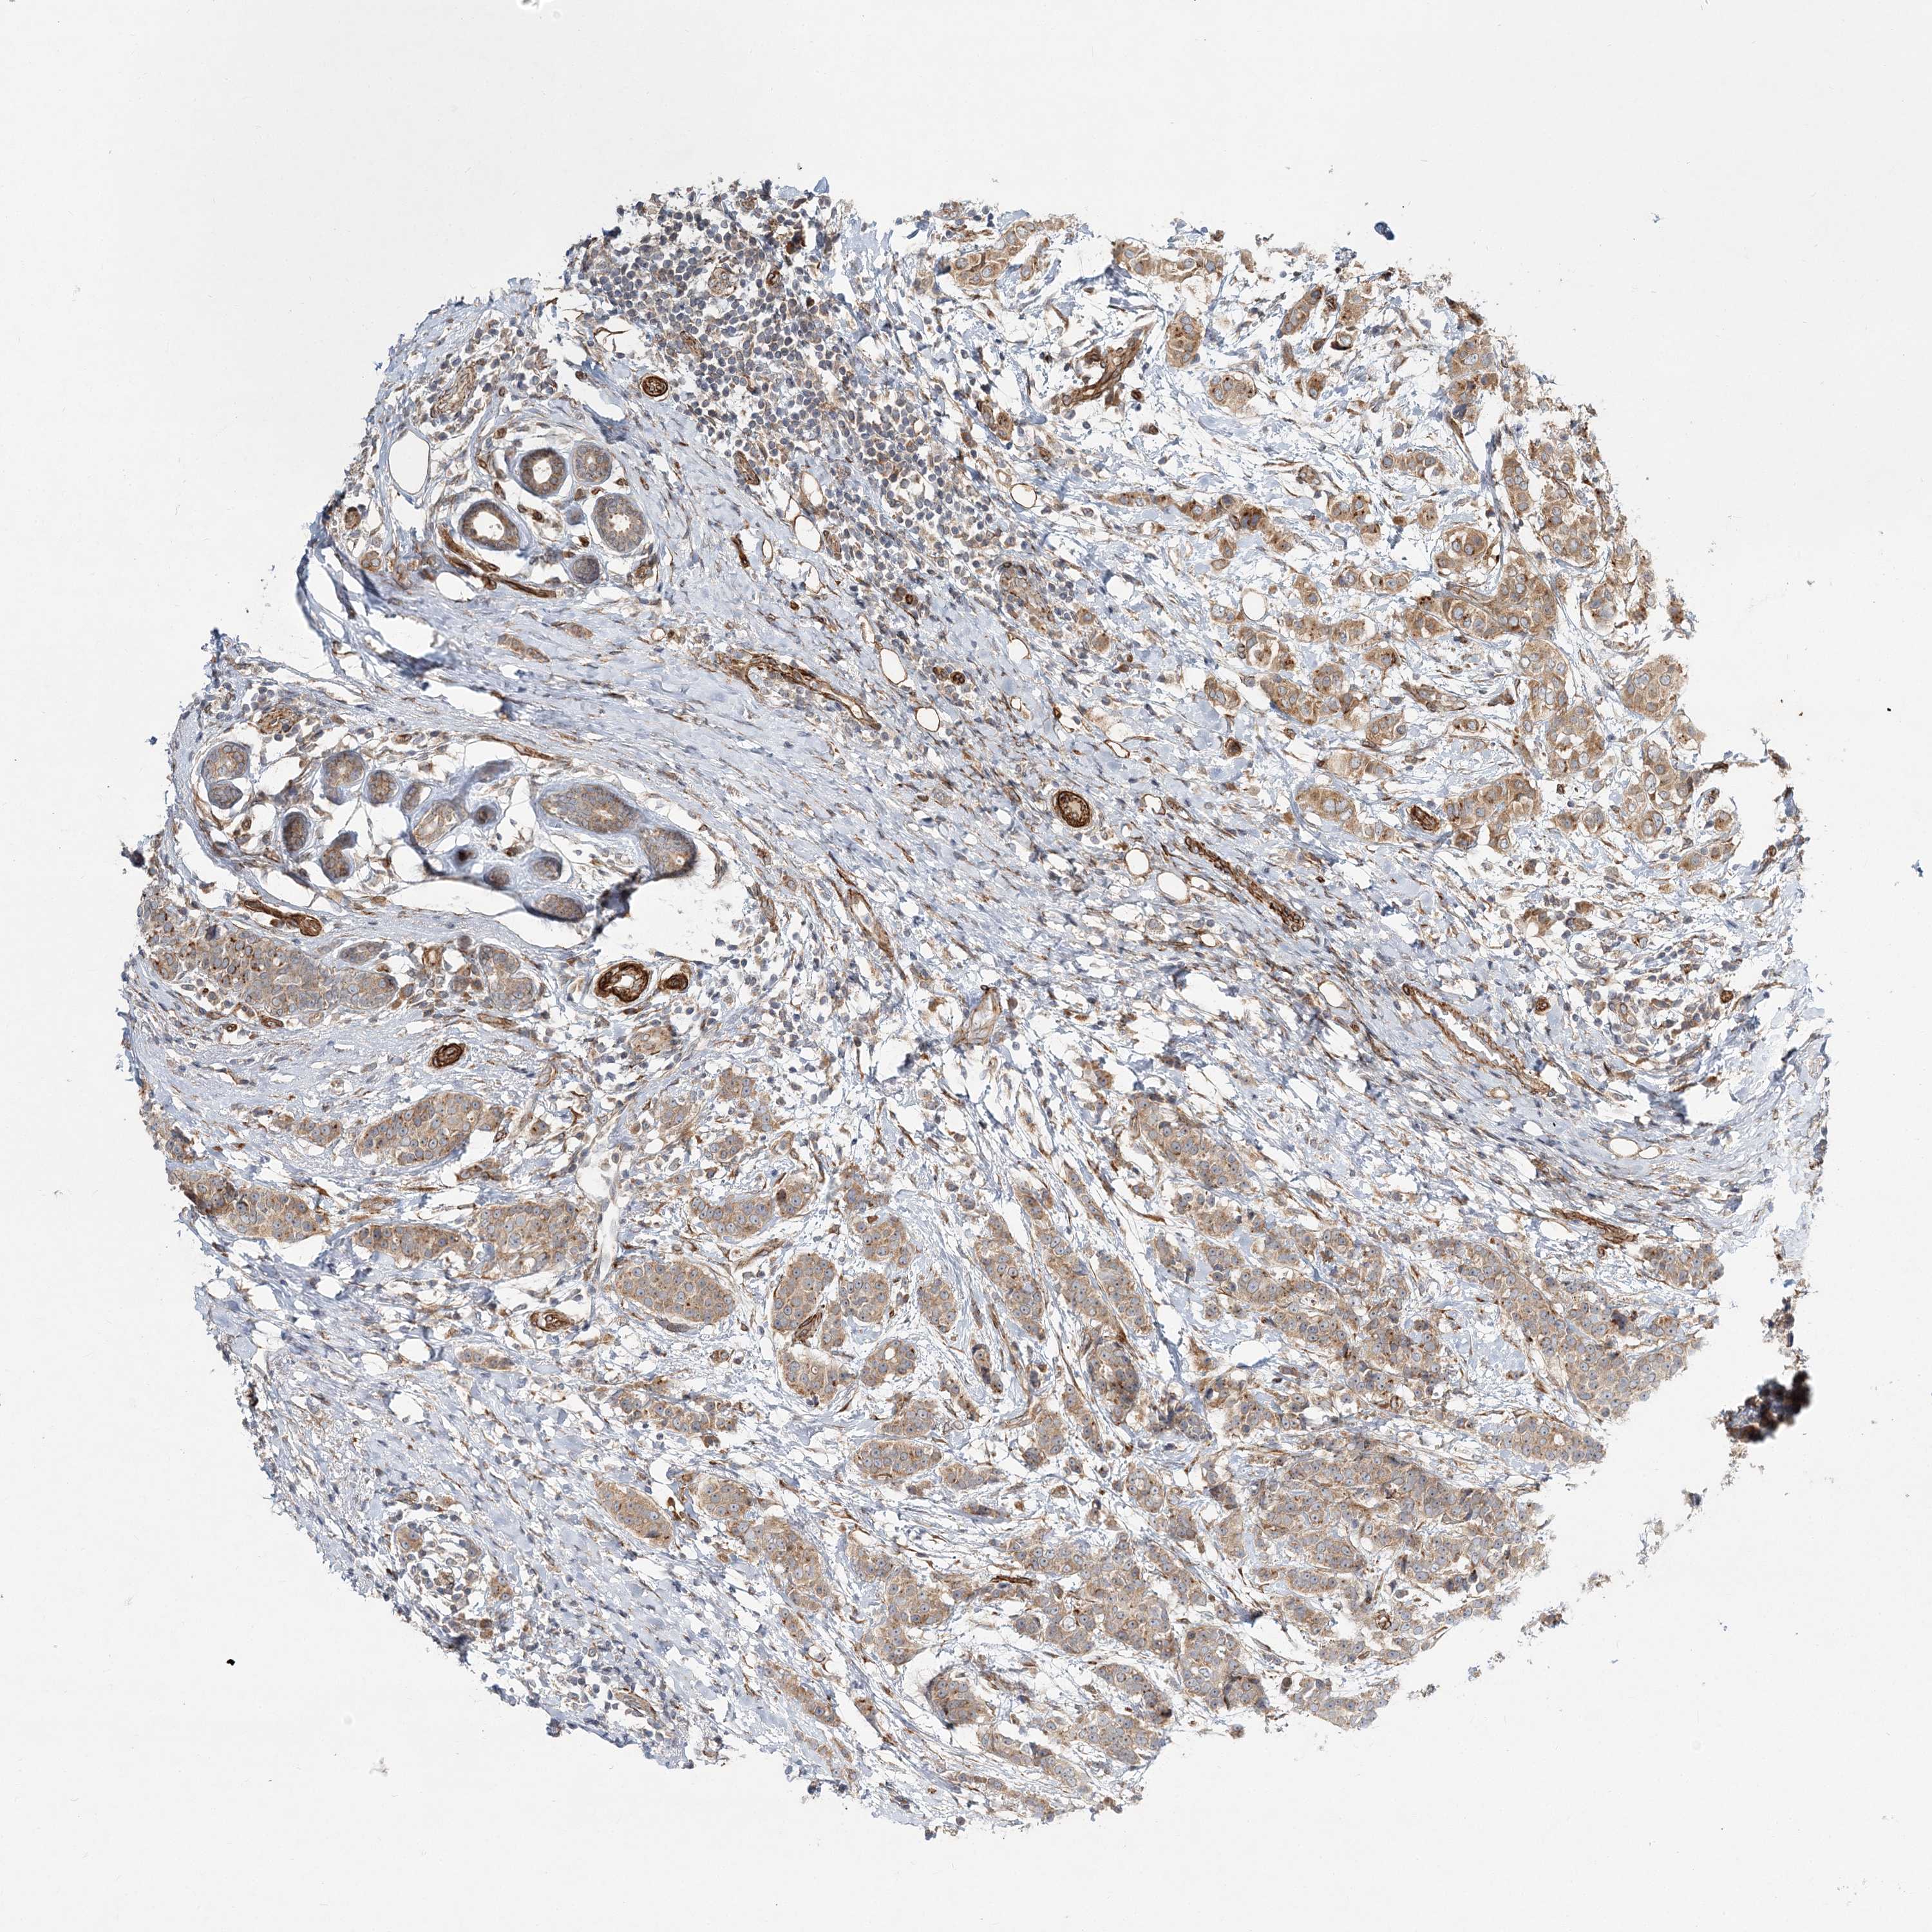

CANCER BREAST CANCER Show tissue menu

BRCA TCGA BRCA VALIDATION PROTEIN EXPRESSION